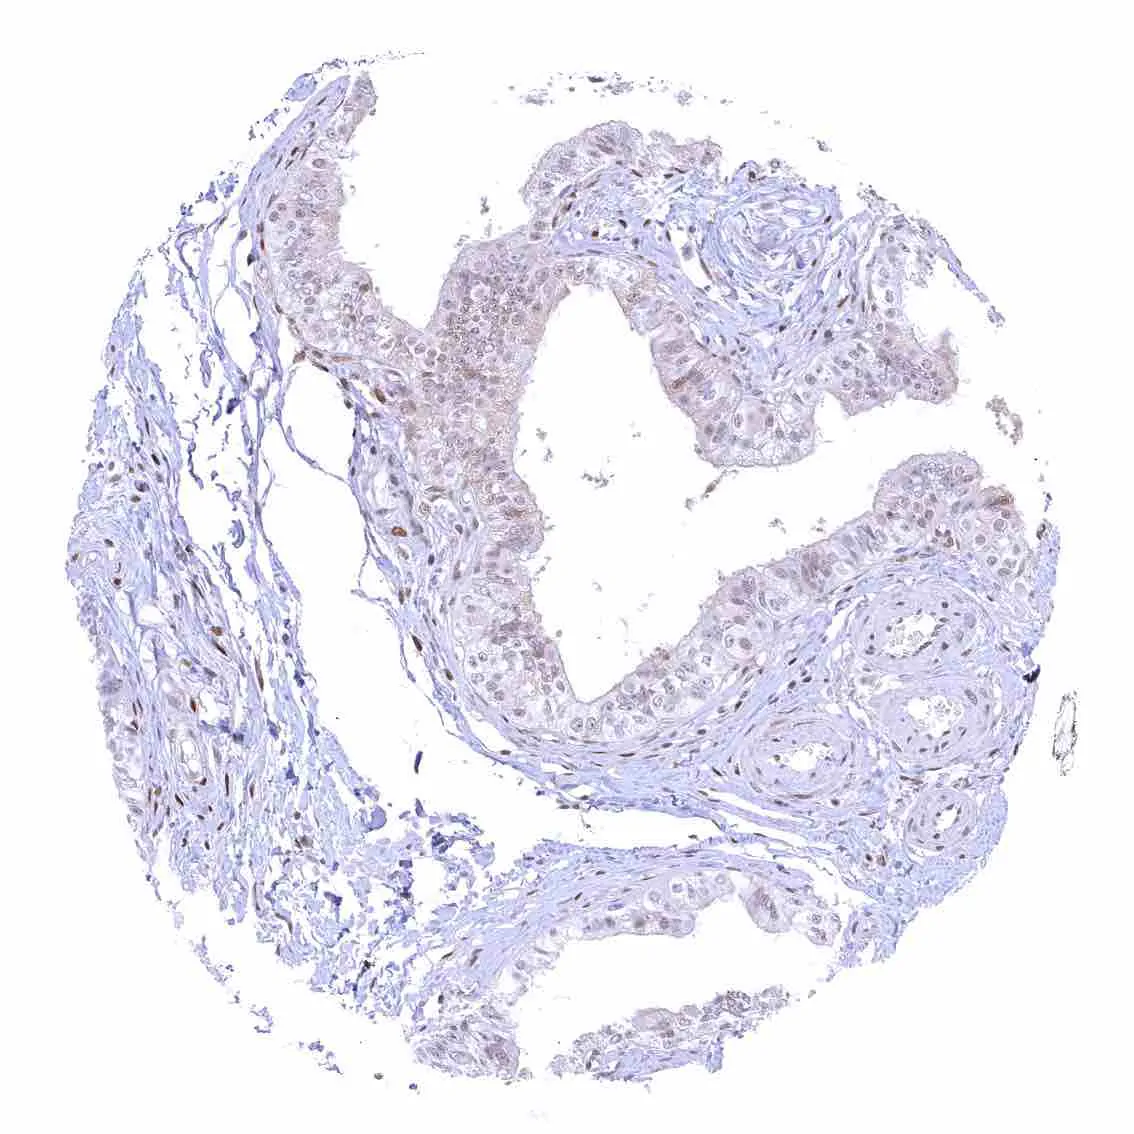

Prostate